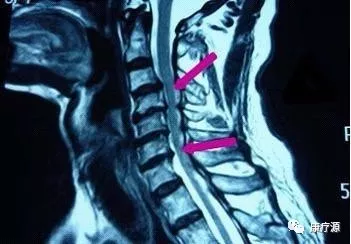

二、脊髓型颈椎病:

如果在慢性颈部疼痛时期,放任自流或者没有得到科学的治疗,那么患者的疾病就会发展,就会在肌肉无力的基础上,发生韧带、骨和椎间盘的退变,患者就会发展为颈椎不稳、骨质增生,产生眩晕、上肢麻木等症状。在此时期,病变累及了椎动脉和神经根,病情比较严重,治疗相对棘手。病情继续发展,就会导致骨质增生严重,椎管狭窄,压迫脊髓,使四肢感觉、运动和大小便功能受到影响,这就是脊髓型颈椎病。此期累及脊髓,非常危险,稍有外伤,甚至一个喷嚏都可能导致瘫痪。